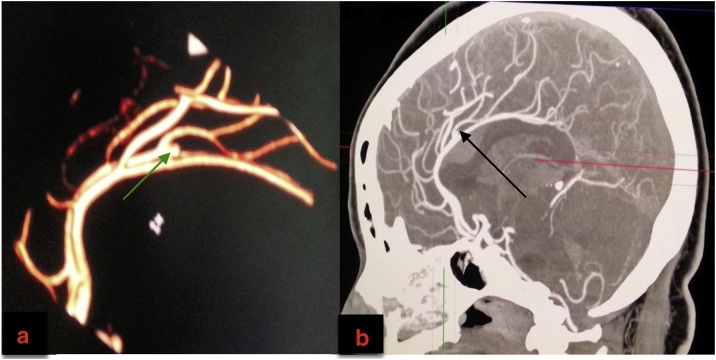

We made a clinical diagnosis of aneurysmal subarachnoid haemorrhage (WFNS grade I). Other differential diagnosis considered in this patient included a ruptured arteriovenous malformation, an intracranial tumour with intralesional bleed and a haemorrhagic cerebrovascular accident. Cranial computerized tomography (CT) scan revealed ICH superior to the body of the corpus callosum, intraventricular extension of this bleed and interhemispheric/parasagittal subarachnoid haemorrhage (Fisher grade IV SAH) (Fig. 1a–c). Cranial CT angiography outlined a small right pericallosal artery aneurysm (Fig. 2a and b).

Fig. 2.

a and b: Cranial Computerized Tomography Angiography.

2a: 3-D Reconstruction (green arrow on the right pericallosal saccular aneurysm).

2b: Sagittal Reconstruction (black arrow showing the same aneurysm).